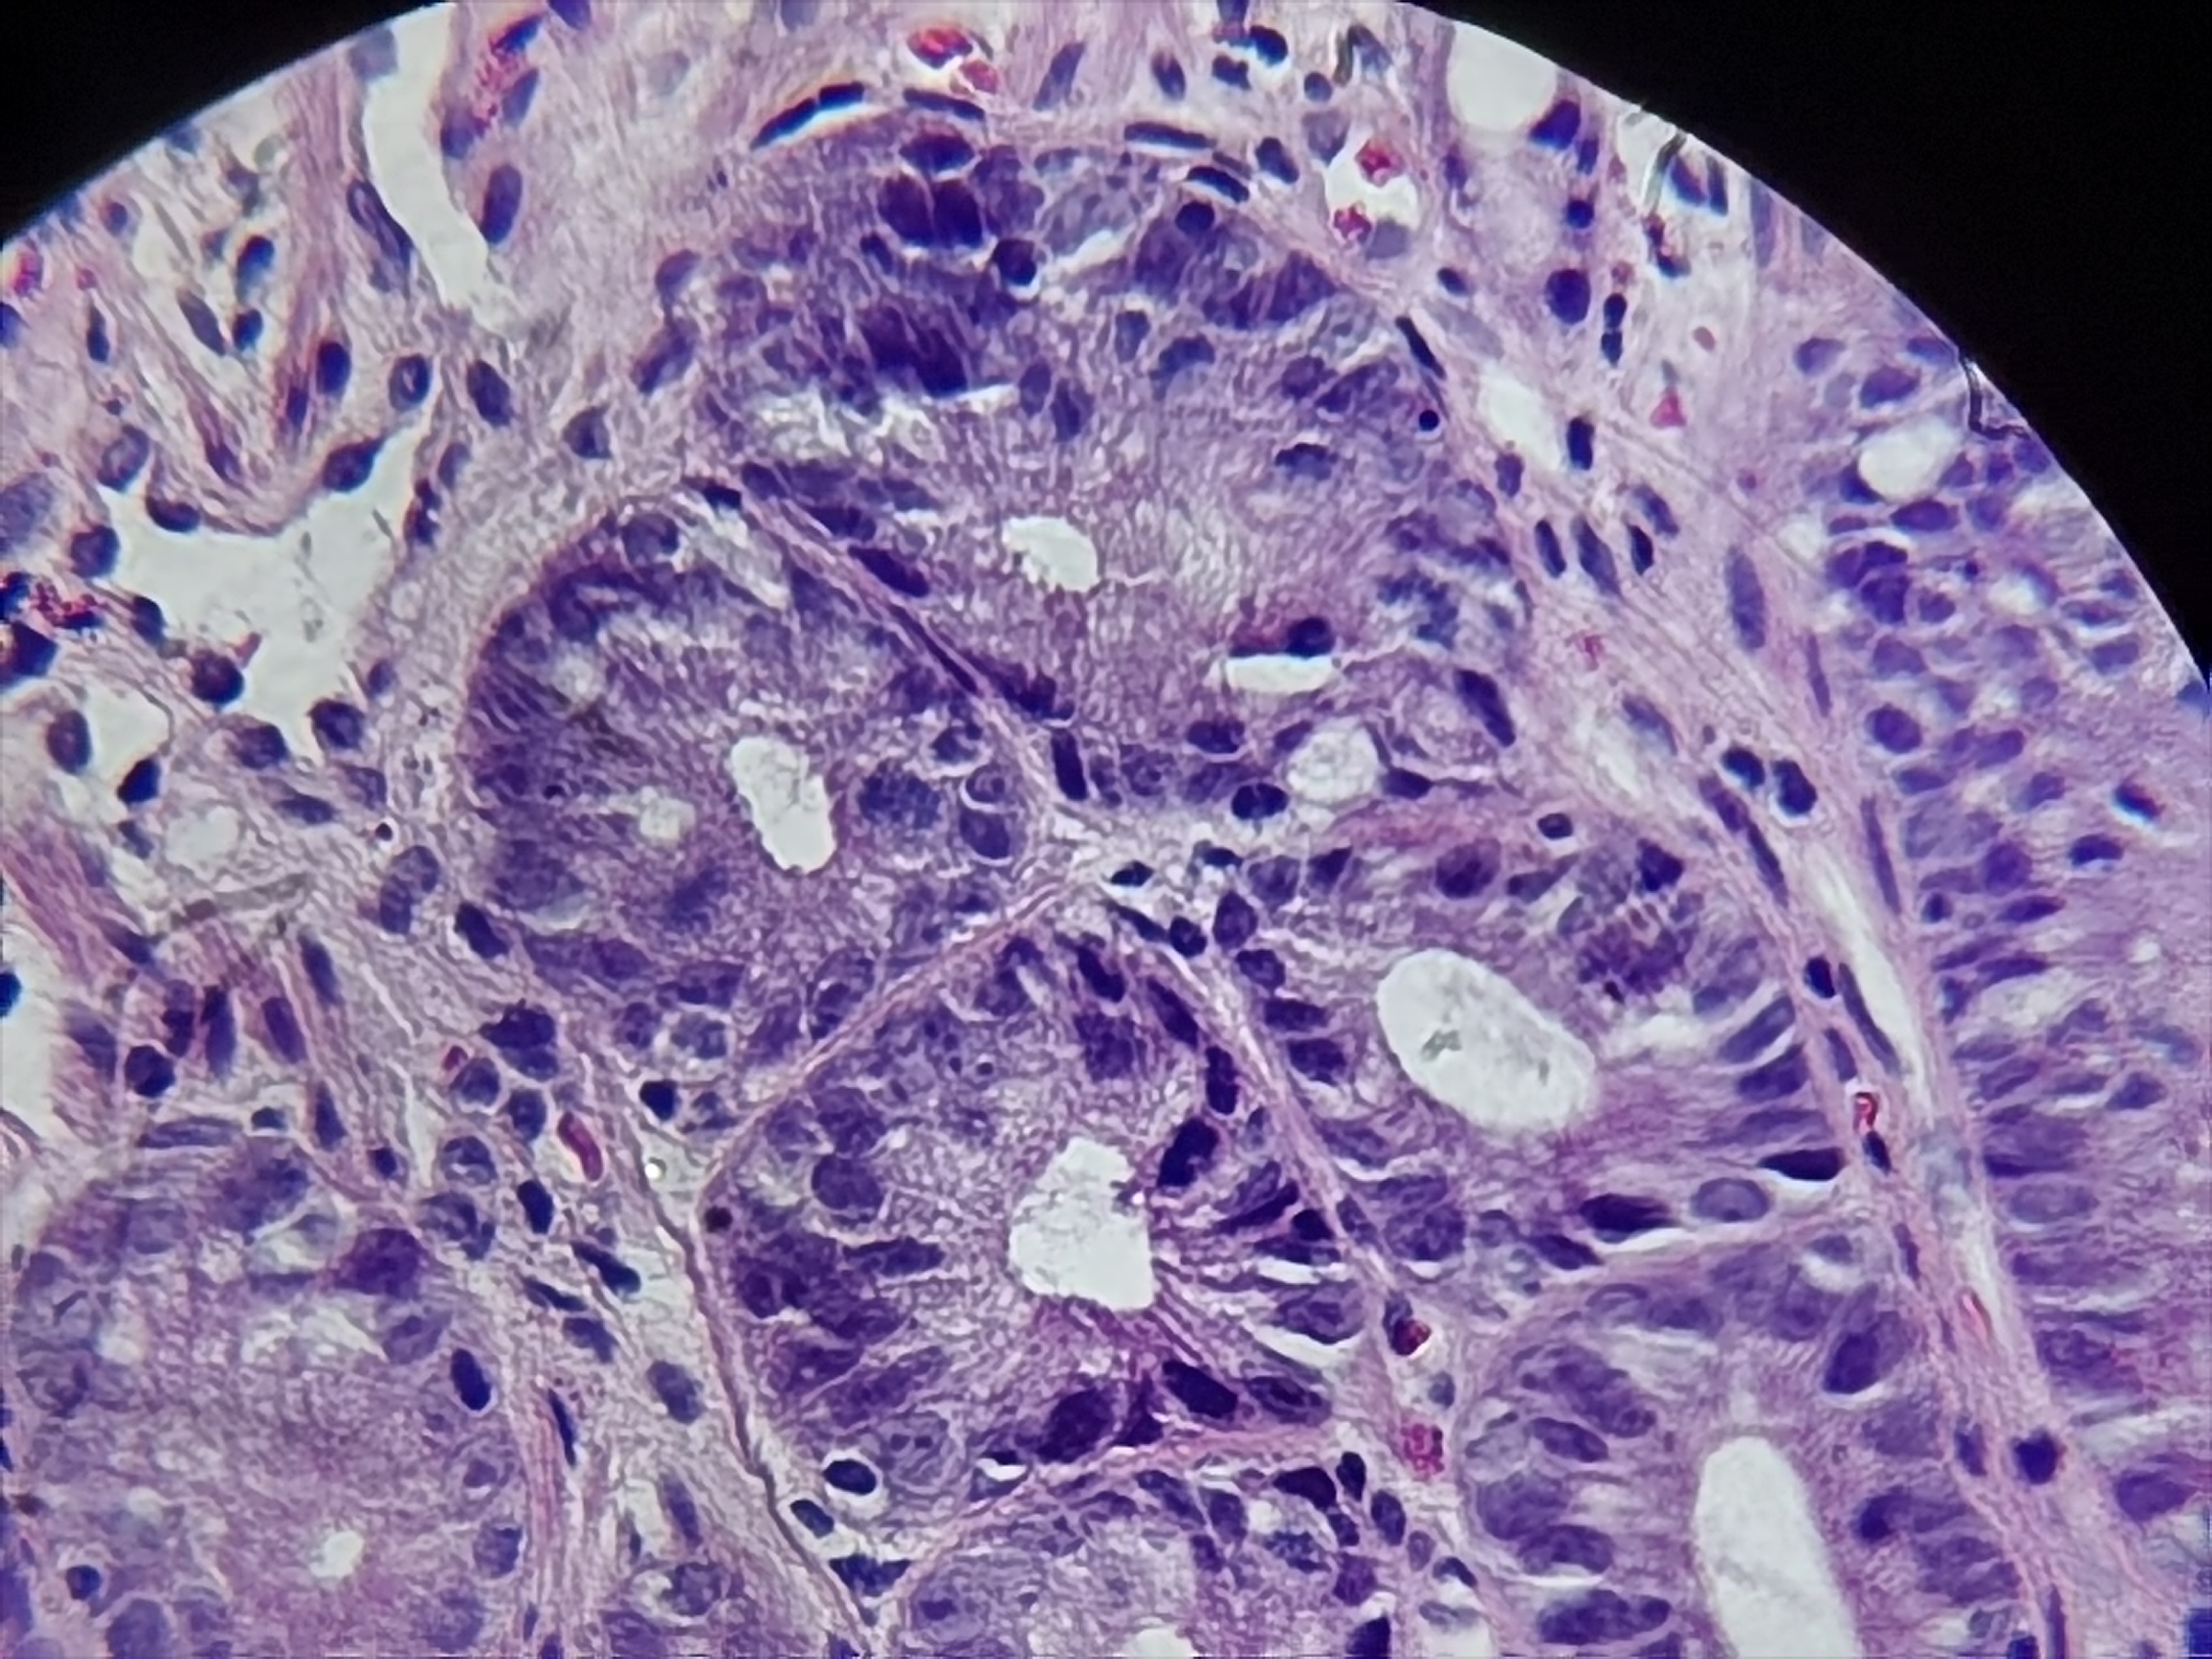

胃窦活检

胃窦:可见散在片状糜烂

胃窦粘膜活检

灰白色组织2块

萎缩+肠化+糜烂

慢性萎缩性炎,伴肠化。